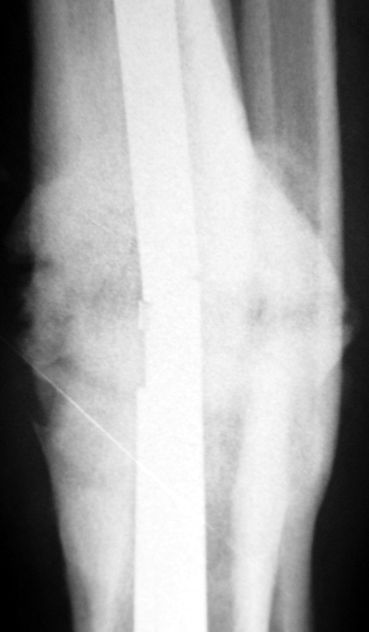

Case 3

Management of Stiff Hypertrophic Nonunions by Distraction Osteogenesis – A Report of 16 Cases